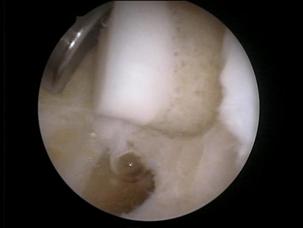

Fig. 1.15 Imagini artroscopice - osteocondrita disecanta: in stinga fragment condral partial detasat , in dreapta patul osos ramas dupa indepartarea fragmentului osteocondral detasat, se observa ca leziunea condrala este mai extinsa decit cea osoasa |

Modificari ale formei si conturului suprafetelor articulare in fracturi, osteocondrita, precum si prezenta de osteofite marginale in artroza (fig. 1.12) pot fi observate in cursul examinarii artroscopice a genunchiului.

Figura 1.16 prezinta o imagine artroscopica a compartimentului extern pe care se observa o fractura a hemiplatoului